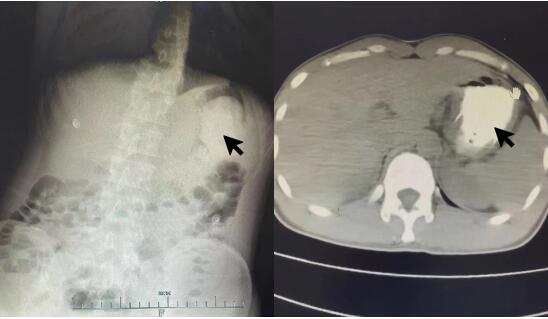

患者接触史明确,诊断为“磷酸铵盐干粉灭火剂中毒”。入院后禁食,胃肠减压,给与保护胃黏膜、抑制胃酸分泌、保护肝功能、导泻、水化碱化以及营养支持对症治疗。根据每日血清电解质结果调整补充量。约1 d后,血磷、血钾、碱剩余恢复正常范围,腹部CT:结肠内高密度影(见图 2)。心脏、双下肢静脉、腹部及泌尿系B超未见明显异常。2 d后外周血白细胞数恢复正常范围。肺部CT示右肺下叶少许炎性灶。3~4 d后血钙、肌酸激酶同工酶、超敏C反应蛋白恢复正常范围。头颅CT及MRI未见明显异常。脑电图示轻中度异常,右侧额颞部中央部略偏胜,脑地形图示右侧额颞部中央部δ频段功率相对偏高。考虑患者口咽部疼痛较前缓解,粪便隐血转阴,改为半流质饮食。5 d后,肌酸激酶恢复正常范围。食管CT:食管局部管壁稍水肿增厚,管腔狭小(见图 3)。患者住院期间未使用抗生素,转氨酶、肌酐均在正常范围,予第6天出院。本病例报道经浙江大学医学院附属第一医院伦理委员会批准,且所有临床资料均获得患者本人授权(伦理审批号:2022380)。

图 3 患者入院5 d后食道CT平扫示食管局部管壁稍水肿增厚,管腔狭小